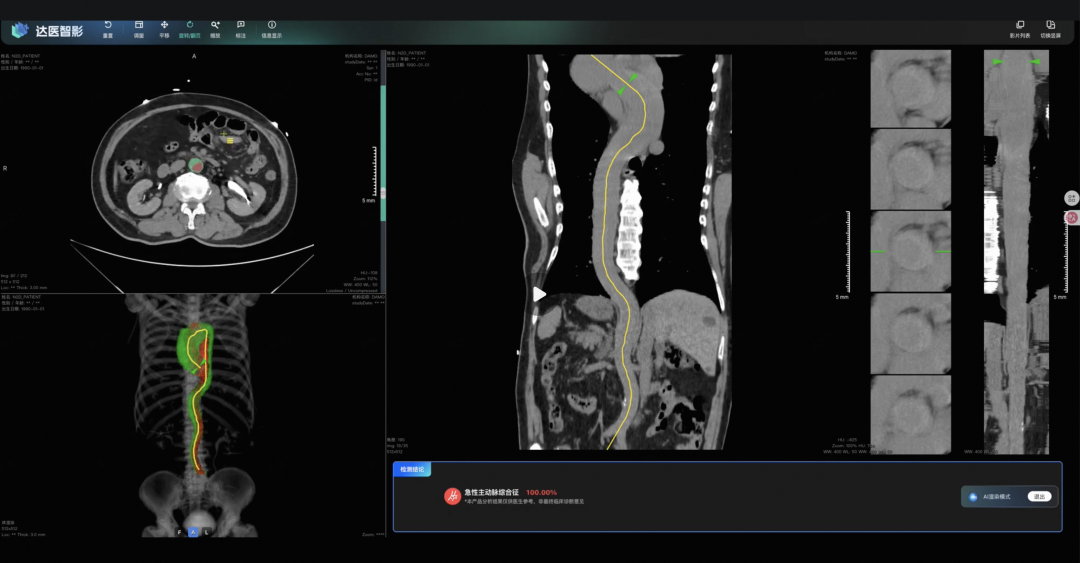

他们的AI模型iAorta真正做到了不可能完成的任务,利用普通平扫CT,精准识别主动脉综合征。

他们把模型部署到了上海一个大三甲医院,在一个为期两个月的临床试验里,AI从一万五千多名胸痛患者中,精准地揪出了21个主动脉综合征患者,敏感性达到95.5%,特异性达到99.4%。

敏感性95.5%,意味着100个真病人,它能找出将近96个,几乎不会漏诊。特异性99.4%,意味着它极少冤枉一个好人,不会给医生添乱。

这里面有个案例特别典型。一个43岁的病人因为上腹部钝痛入院,医生初步怀疑是胆囊结石,就开了个上腹部的平扫CT。结果片子刚拍完,大概3分钟,iAorta就报警了,说主动脉有夹层的迹象。

医生马上跟进做了增强CT,确诊!整个过程只用了94分钟。

如果没有AI,这个病人很可能就被当成胆囊结石收治入院了,等到血管破裂,一切都晚了。